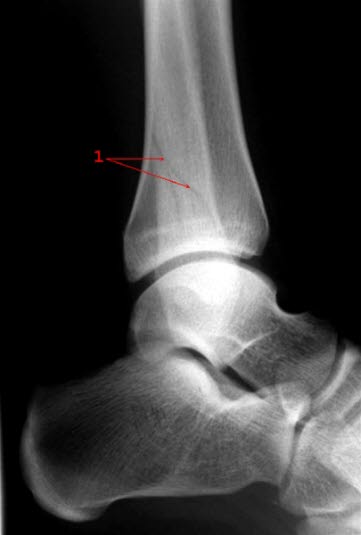

Malleolfraktur, side

Skråfraktur gjennom laterale malleol uten feilstilling (1)